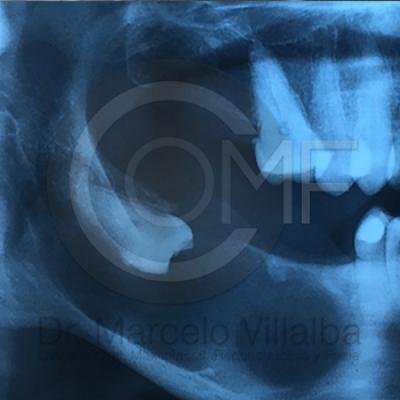

Patología

Patologia1